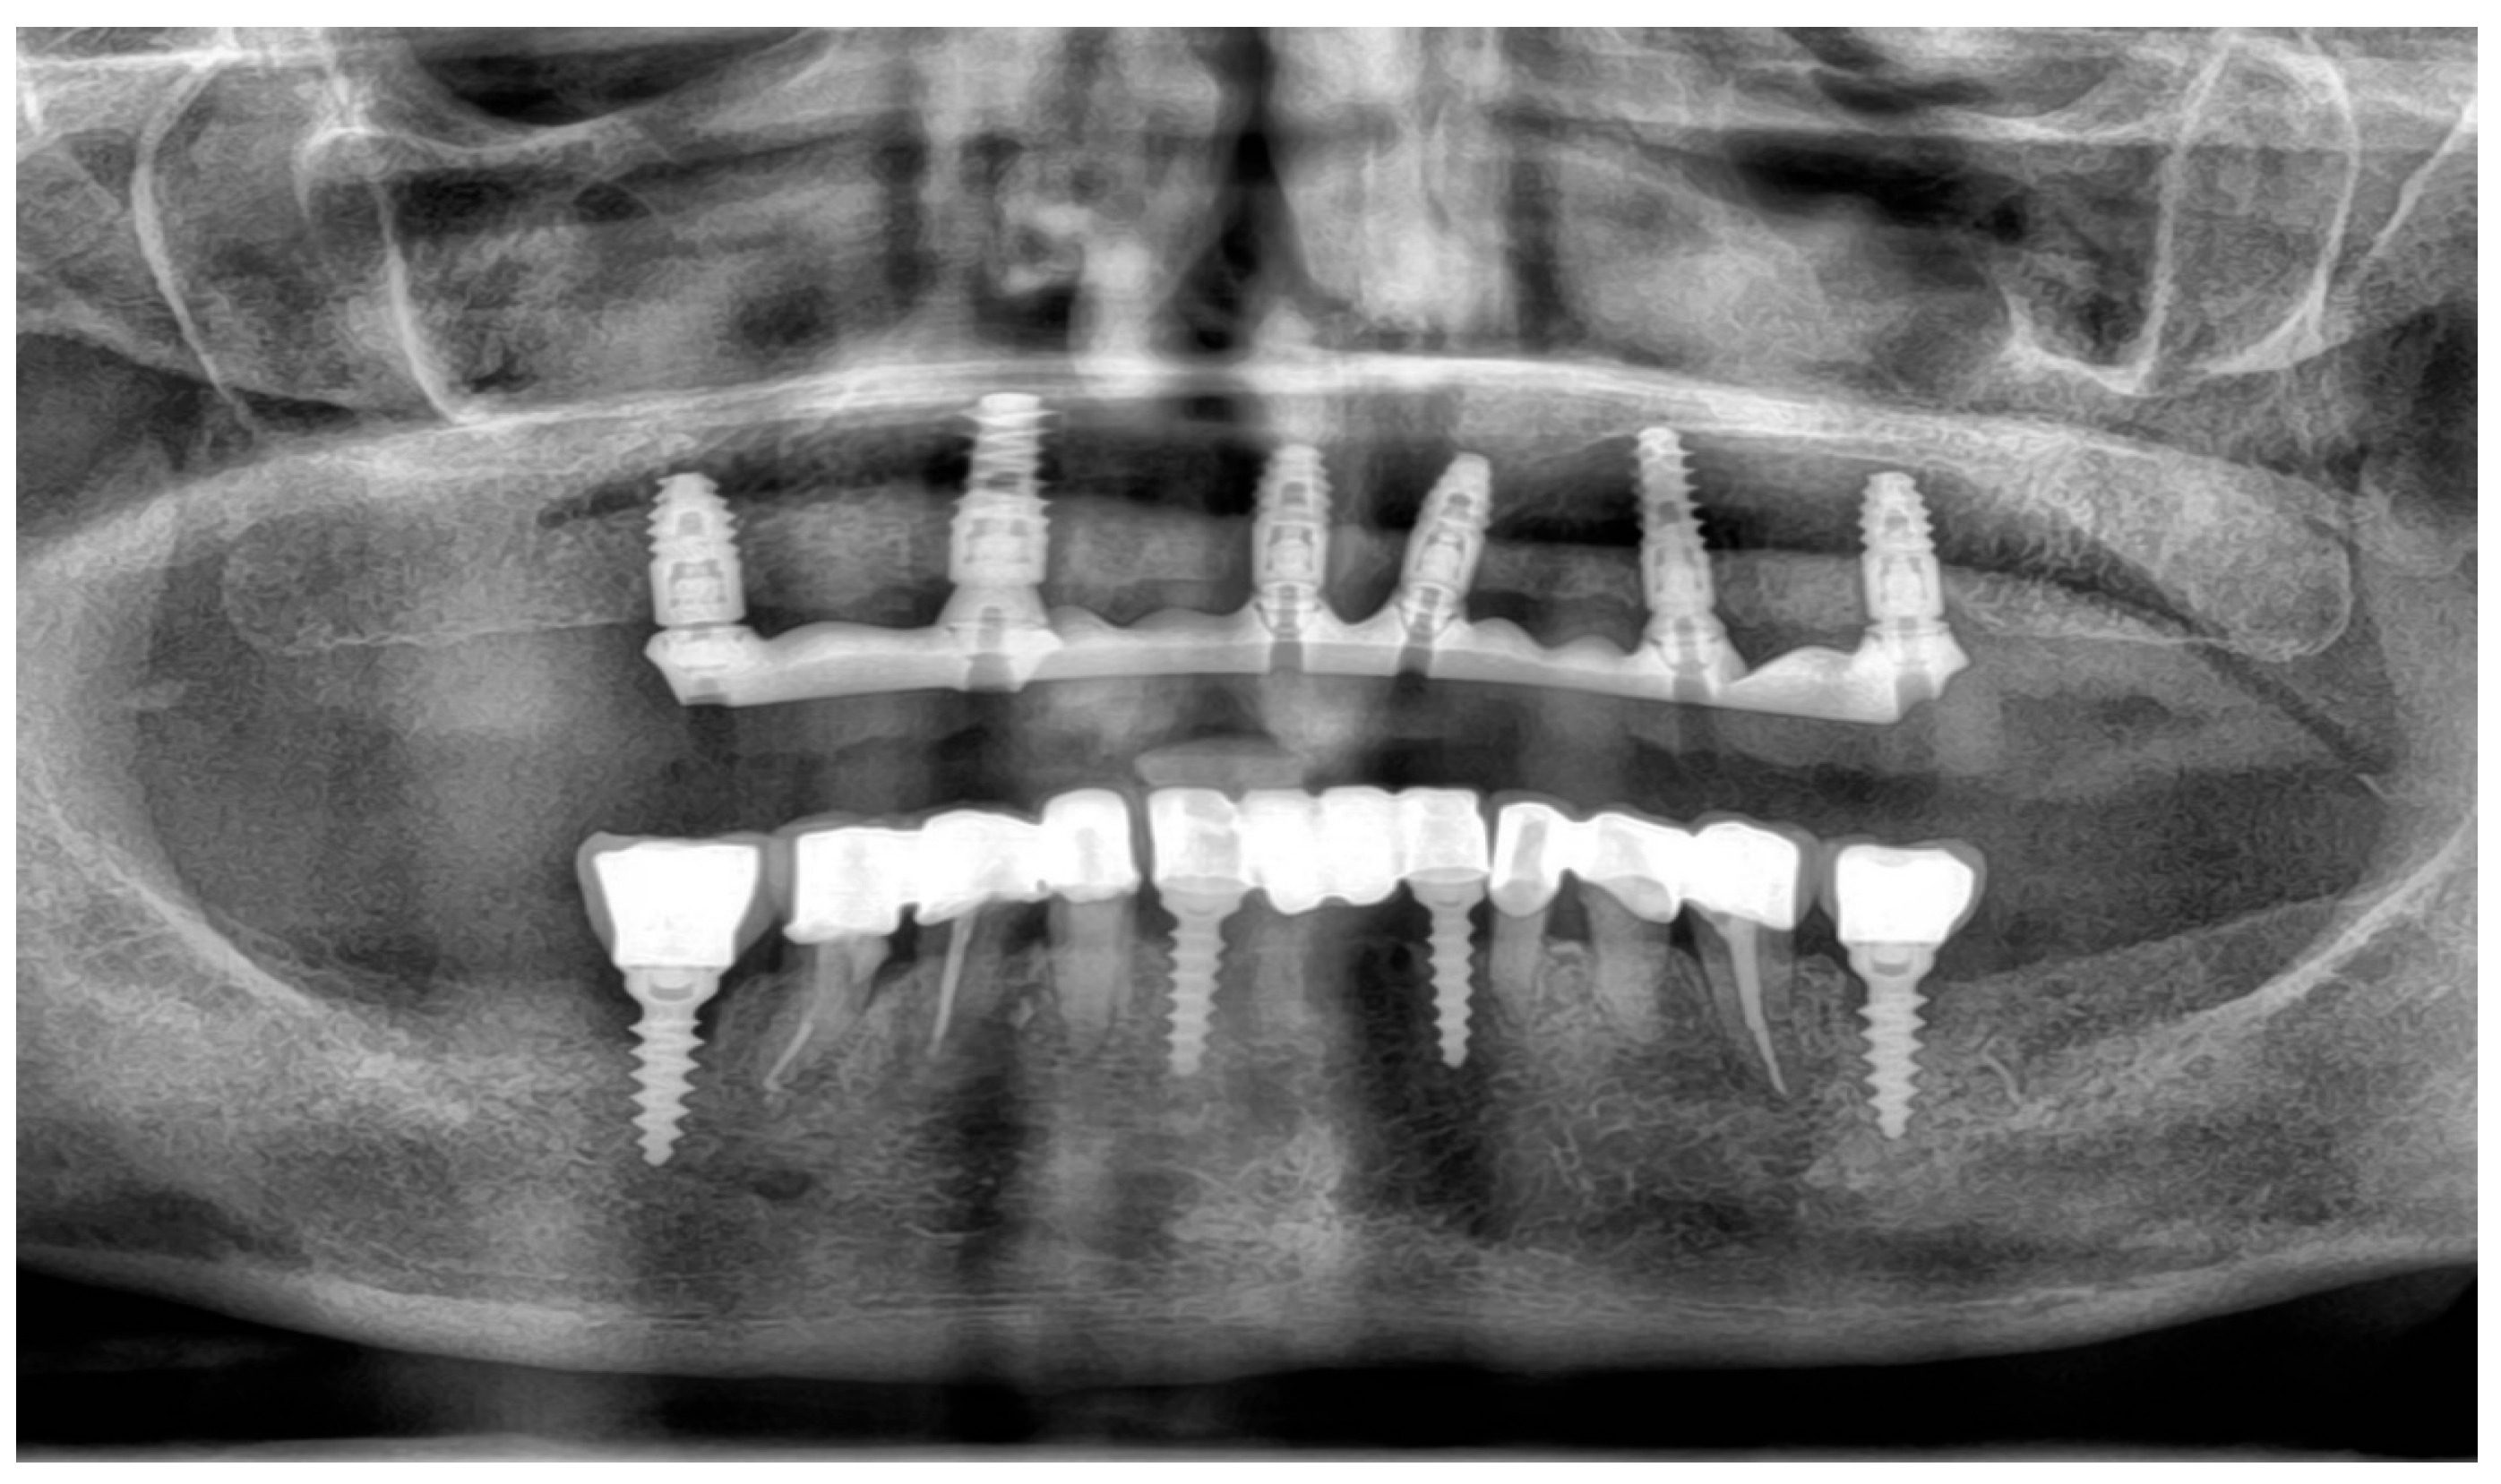

To supplement the clinical findings, a cone beam computed tomography (CBCT) scan was obtained (Figure 1) and evaluated. The implants existing in the maxilla demonstrated proper surrounding bone architecture. The compromised status of the remaining teeth was confirmed. In addition, the available bone conditions in the regions of teeth 14 and 24 were assessed to be adequate for future implant placement, particularly in the context of immediate implant insertion. This is in accordance with the literature emphasising that sufficient bone volume, labial plate integrity, and socket morphology, are critical prerequisites for successful immediate implant placement [7,8,9].

Figure 1. Preoperative panoramic reconstruction from CBCT, showing the initial condition of the existing tooth- and implant-supported restorations in the maxilla and mandible, as well as the visualisation of two planned implants in positions 14 and 24.